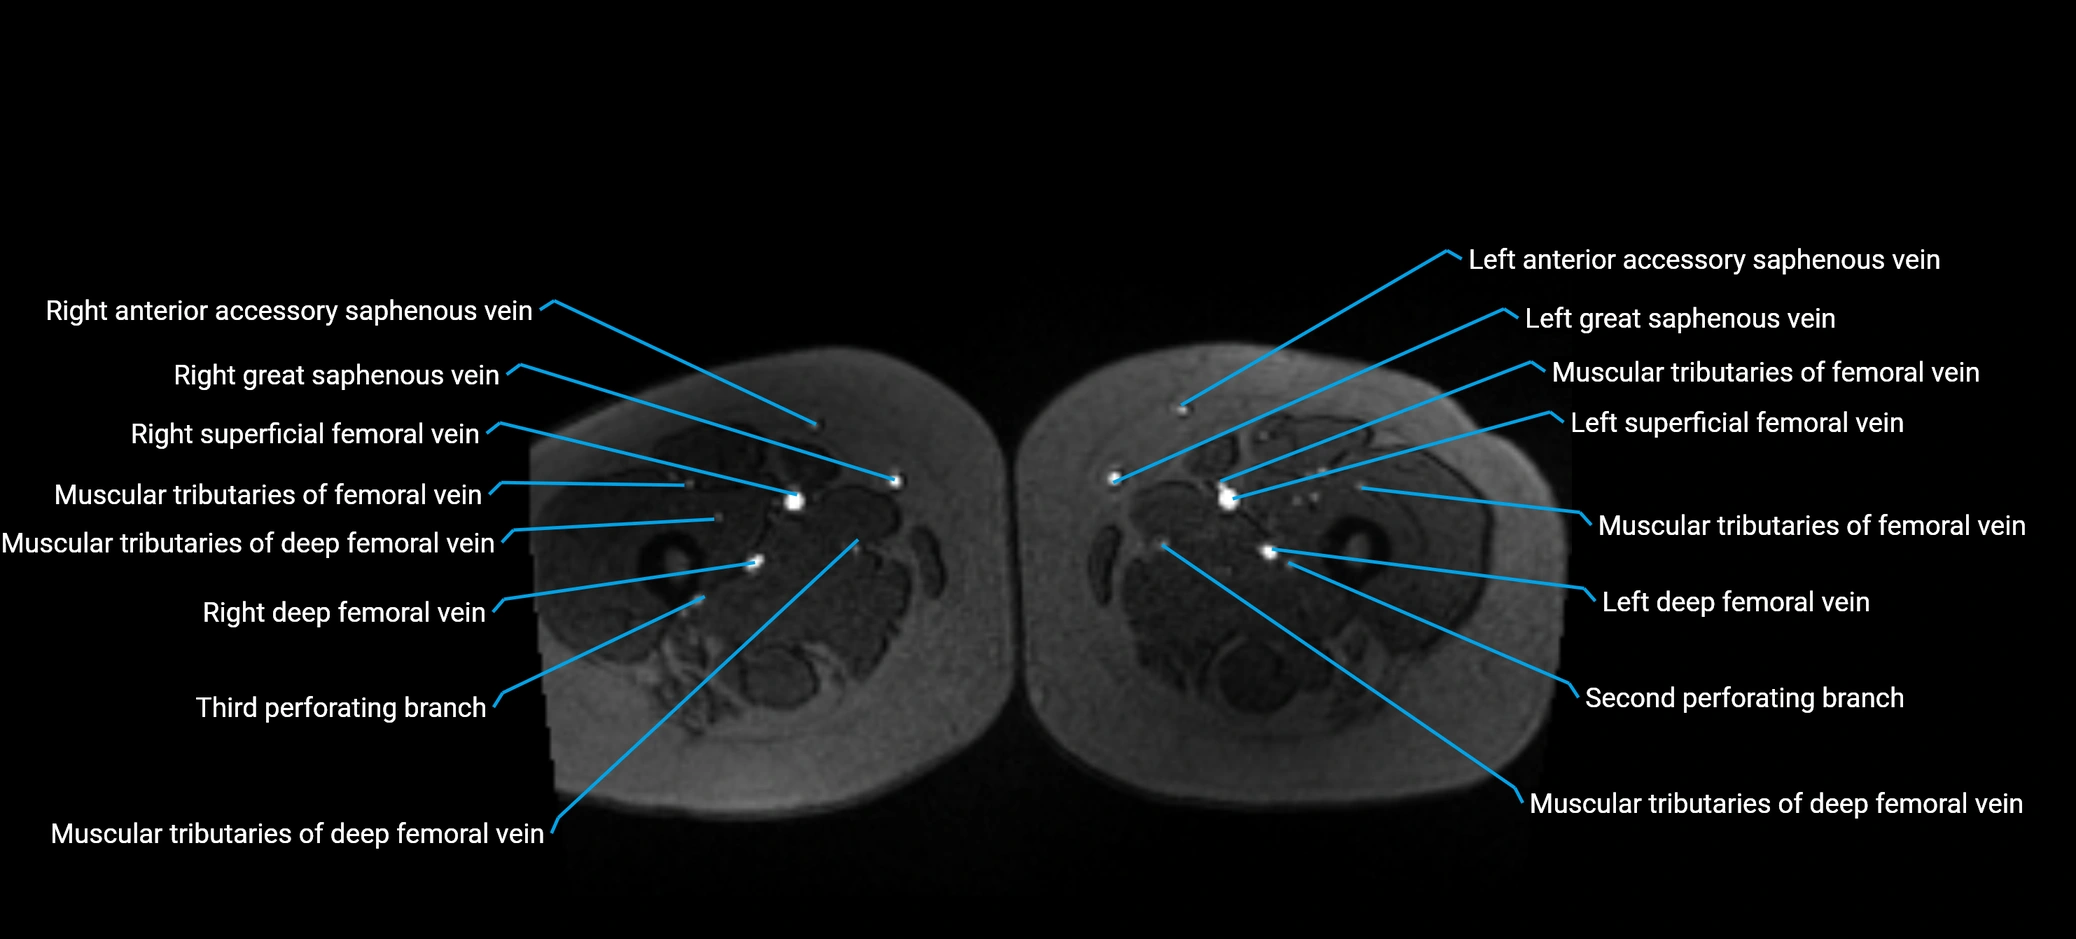

MRV TOF (Time-of-Flight MR Venography):

• Appears as a bright, high-signal vascular channel representing flowing blood

• Clearly shows branching pattern of right portal vein into anterior and posterior branches

• Best in coronal or axial reconstructions for segmental mapping

• No need for contrast, relies on flow-related enhancement